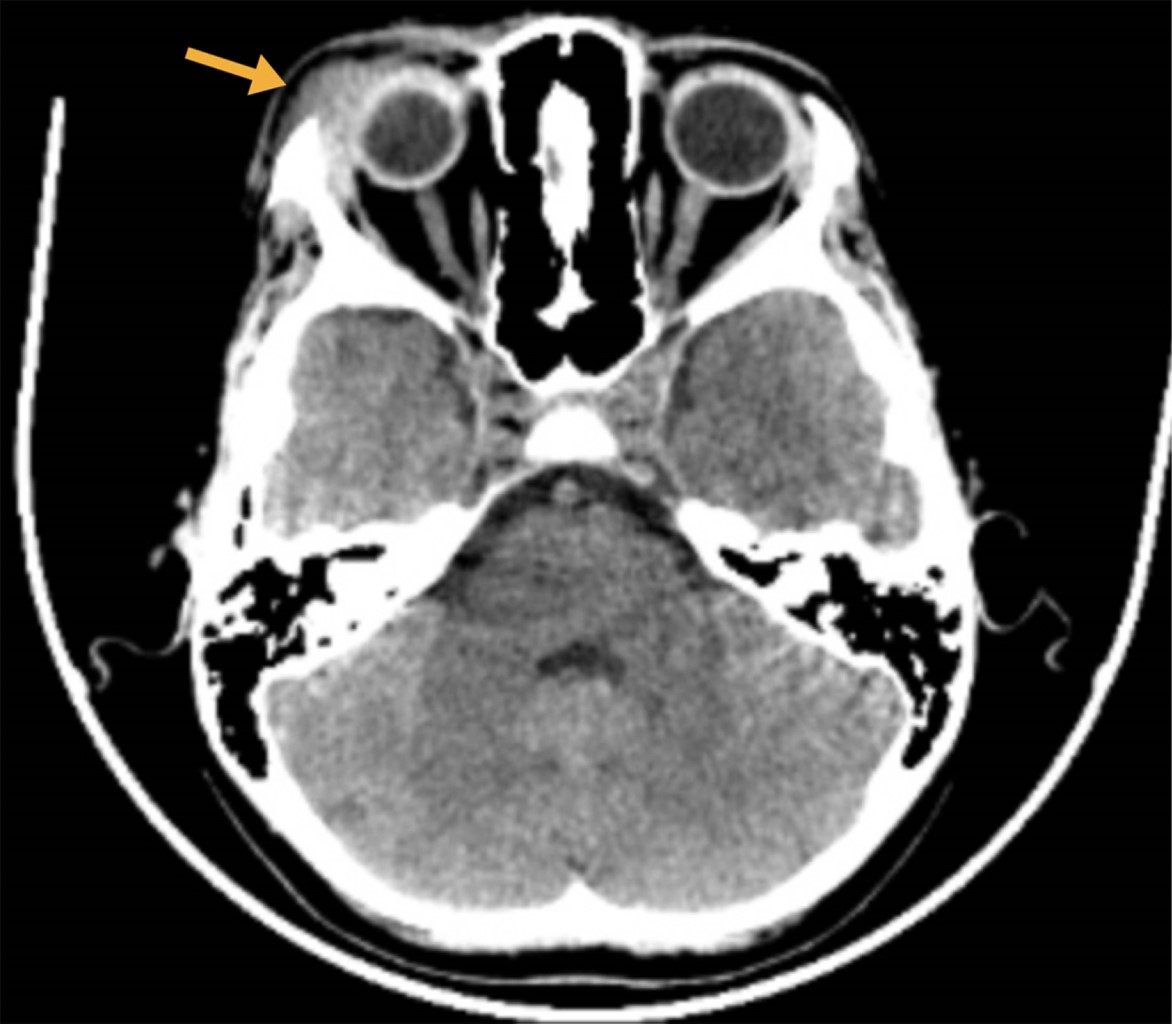

Se realizó una tomografía computarizada (TC) de la región craneal, la cual reveló una lesión lítica en la región frontoorbital, con dimensiones aproximadas de 24 × 19 × 30 mm, que incluía una porción de tejido blando (Figura 2).

El diagnóstico de la enfermedad de Erdheim-Chester del caso que reportamos se realizó a partir de la evaluación clínica, hallazgos de imagen y análisis histopatológico. Las imágenes revelaron una lesión lítica en la región frontoorbital con un componente de tejido blando, mientras que por histopatología se demostró proliferación de histiocitos espumosos, características de esta enfermedad. Es de señalar que, en comparación a los reportes de adultos, el cuadro clínico fue menos agresivo y más localizado. Lo anterior, hace suponer que, en el ámbito pediátrico, esta enfermedad puede ser de mejor pronóstico con menor riesgo de pérdida visual.